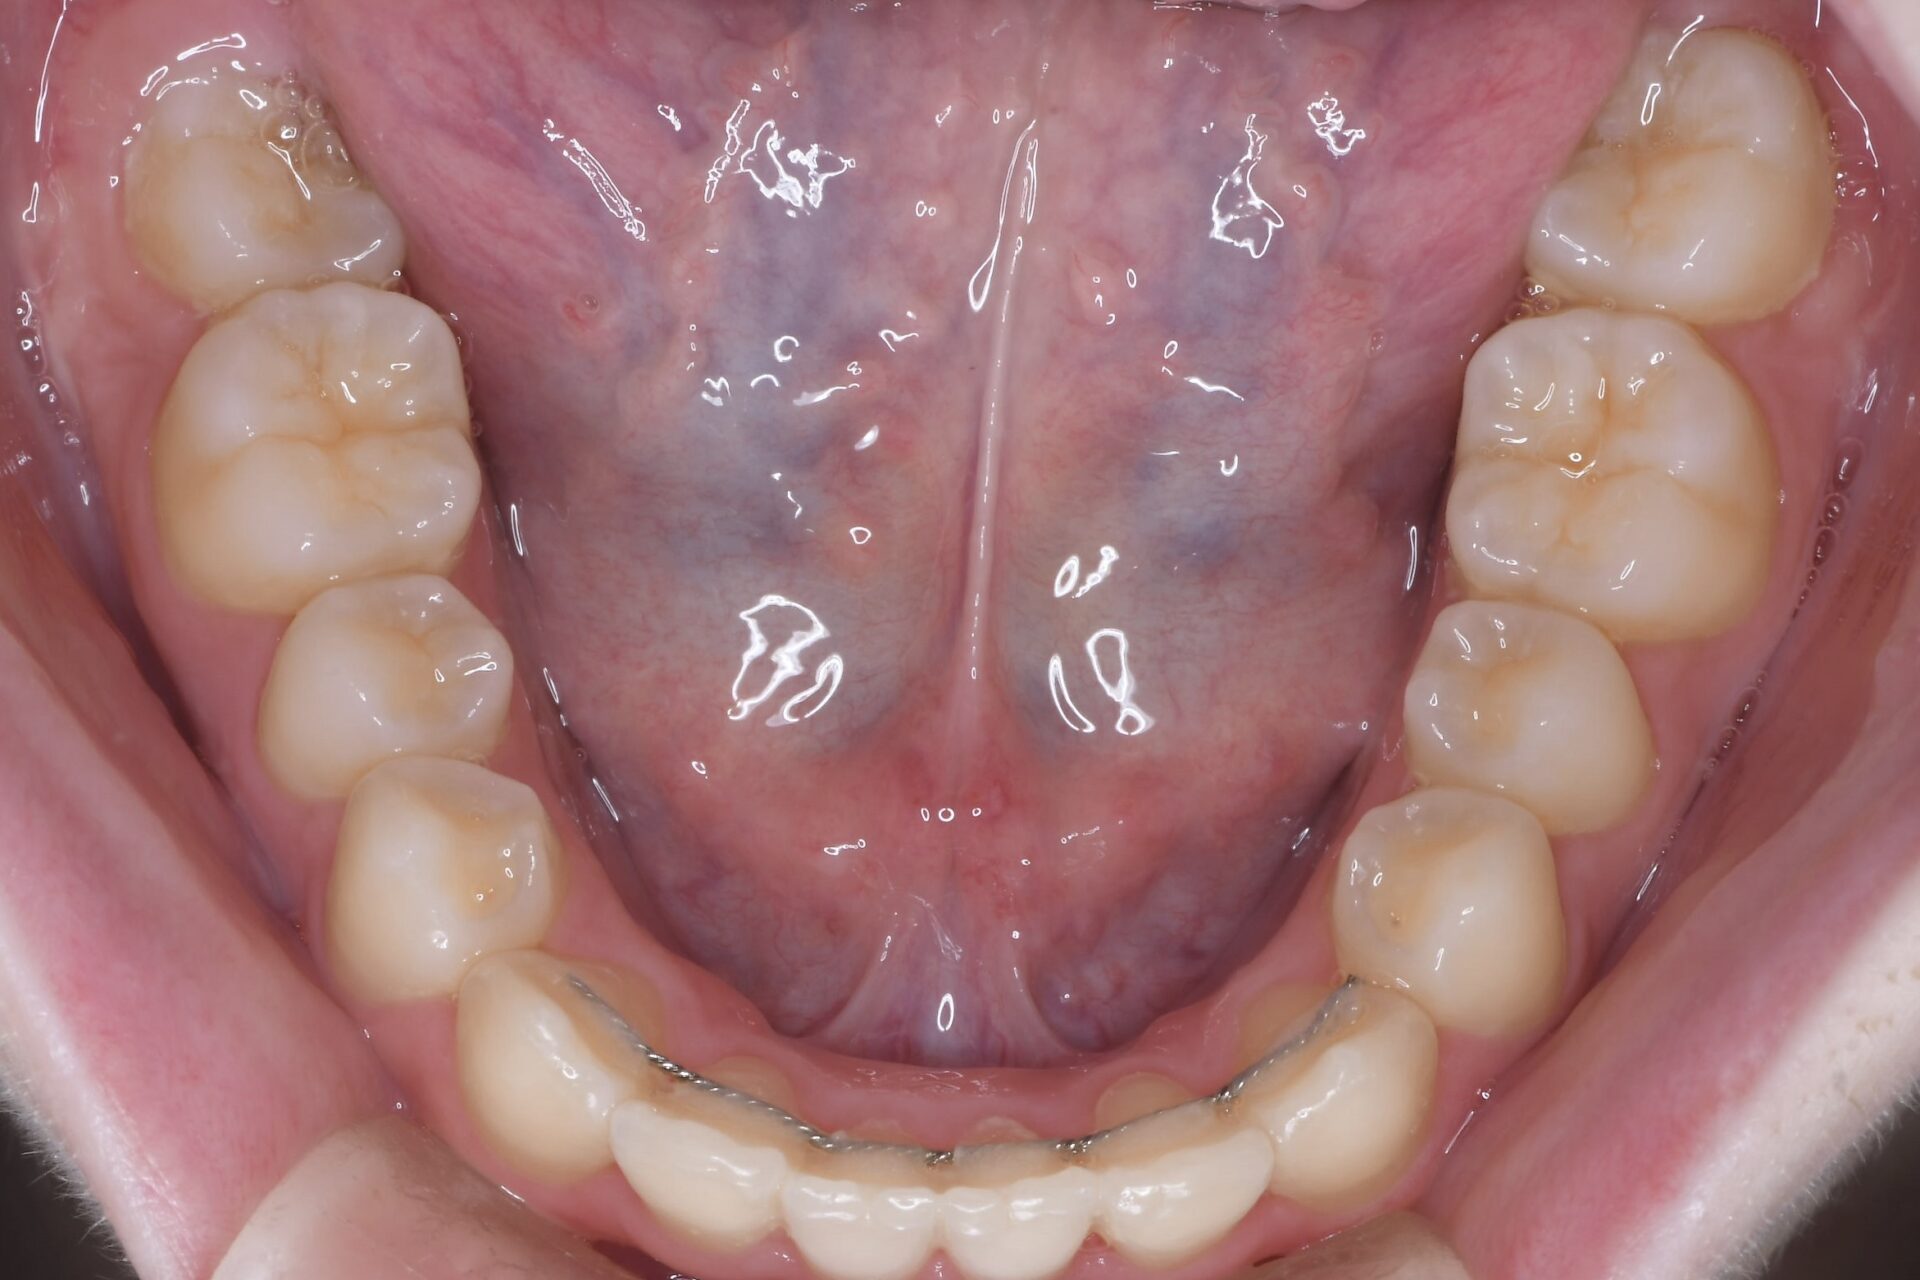

メインテナンス時(下顎)